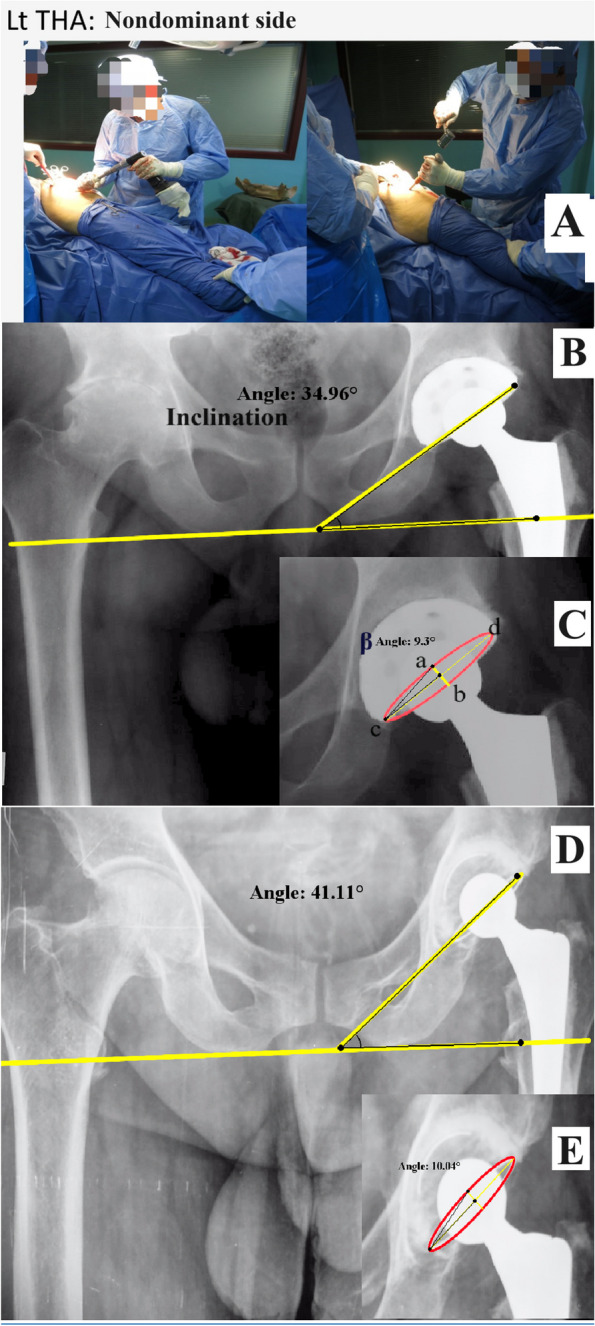

Methods: Cup inclination and anteversion of 420 THAs were radiographically evaluated retrospectively. THAs were performed by a senior right-handed surgeon, who operated through a direct lateral approach in a lateral decubitus position using manual instruments and freehand technique for cup placement. Patients were assigned to two groups: Group A (right, or dominant side), and Group B (left, or non-dominant side), with equal cases of THAs (n = 210) in each group.

Results: No difference was found in patients' basic characteristics, preoperative diagnosis, and cup fixation (54.3% cemented and 45.7% cementless) between the two groups. There was a significant difference in cup inclination between Groups A and Group B (40.1° ± 6.3° vs. 38.2° ± 6.1°) (P = 0.002). No significant difference was revealed in anteversion between the two groups (11.7° ± 4.4° vs. 11.8° ± 4.7°) (P = 0.95). The percentage of cups located within the safe zone in terms of both inclination and anteversion was 85.2% vs. 83.8% and 69% vs. 73.3% for Group A and Group B, according to Lewinnek and Callahan's safe zones, respectively. There existed a significant difference in the cemented cup inclination between Group A and Group B (40.8° ± 6.4° vs. 38.3° ± 6.3°) (P = 0.004).

Conclusion: Cup inclination is affected by the surgeon's handedness when operating through a direct lateral approach and using a freehand technique, while anteversion is less affected. Furthermore, the difference is greater with cemented cups.